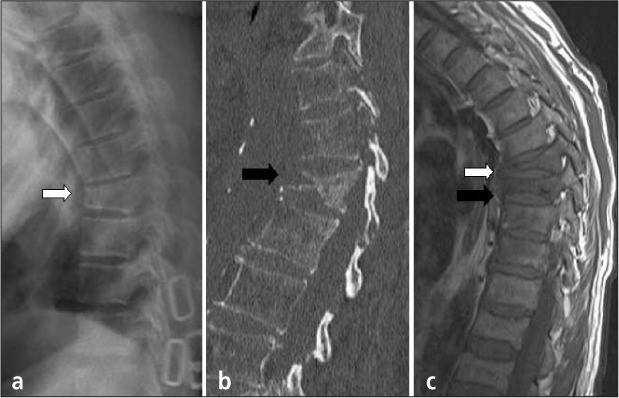

- Chụp X-quang: Để xác định tình trạng các đốt sống và nguyên nhân khác gây kích thích rễ thần kinh (nếu có) như gãy xương, thoái hóa đĩa đệm hoặc gai cột sống.

- Chụp CT hoặc CAT kết hợp chụp tủy đồ của cột sống: Để hiển thị chi tiết tình trạng xương của người bệnh.

- Chụp cộng hưởng từ (MRI): Phương pháp này có thể cho thấy tủy sống, rễ thần kinh và các vùng xung quanh, cũng như nguy cơ xuất hiện của phì đại, thoái hóa và các khối u.